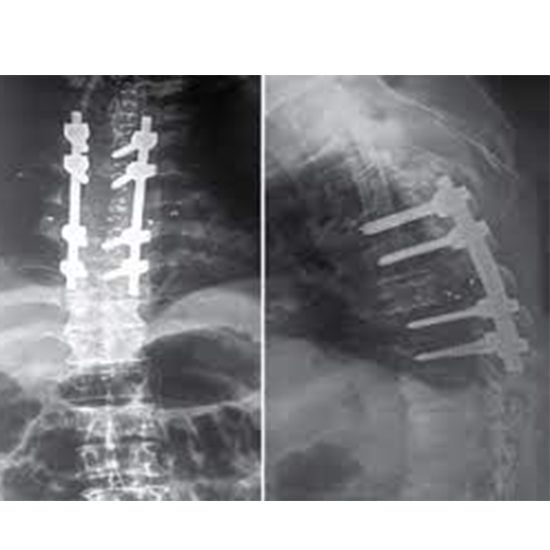

What is an X-ray Dorsal Spine AP & Lateral View Test?

This X-ray shows the dorsal/thoracic spine, which comprises twelve vertebrae and forms the central backbone.